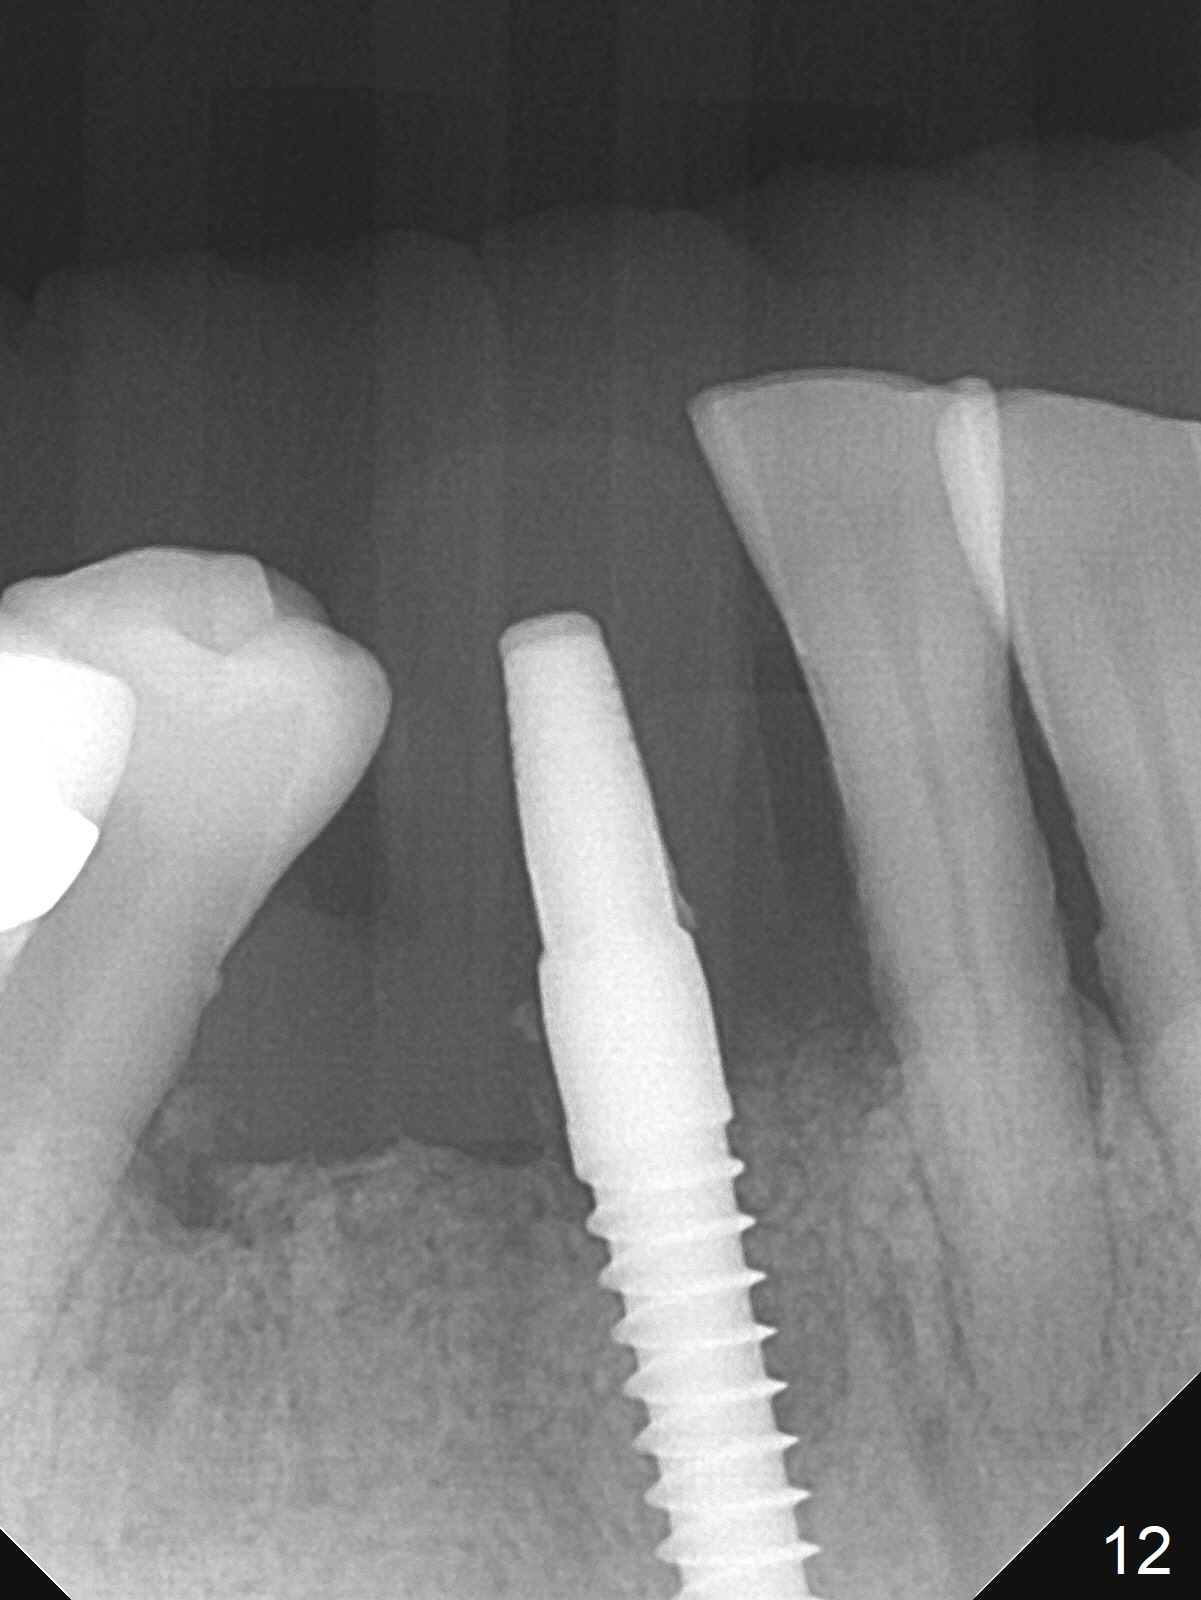

The lower dentition is special, consisting of a residual root (Fig.1 ^), 2 incisor (I), 1 canine (C), 1 premolar (P) and 1 molar (M). The residual root looks like an incisor with rotation of 90º (Fig.2,3). Osteotomy is initiated (Fig.4) for a 3x16(2) mm 1-piece implant (Fig.5 with 45 Ncm). The implant is being placed as distal as possible (Fig.4 arrow) so that a large canine-like provisional is to be fabricated in the large edentulous space (Fig.8,9) after bone graft (Fig.6,7 *). The gingiva around the provisional (Fig.10 P) remains healthy 11 days postop with occlusal clearance against the opposing dentition (Fig.11). The implant threads are not exposed with the help of bone graft 3 months 1 week postop (Fig.12). The gingiva around the implant is healthy (Fig.13). Soft tissue socket is formed by the provisional (Fig.14 *).